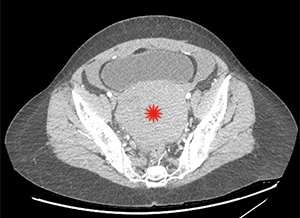

Question 1 : What’s wrong with these pictures?

There is a large hemoperitoneum (arrow below) with a massive rectouterine structure (star below) concerning for clot.

We were most concerned about a ruptured ovarian cyst as the patient’s pregnancy test was negative and there was no other obvious cause of blood in the abdomen. She did not have the classic story of onset of pain after intercourse. We did a CT scan because the bedside ultrasound images were difficult to interpret due to the clotted blood. The radiologist suspected ruptured ovarian cyst as the cause of the hemoperitoneum.